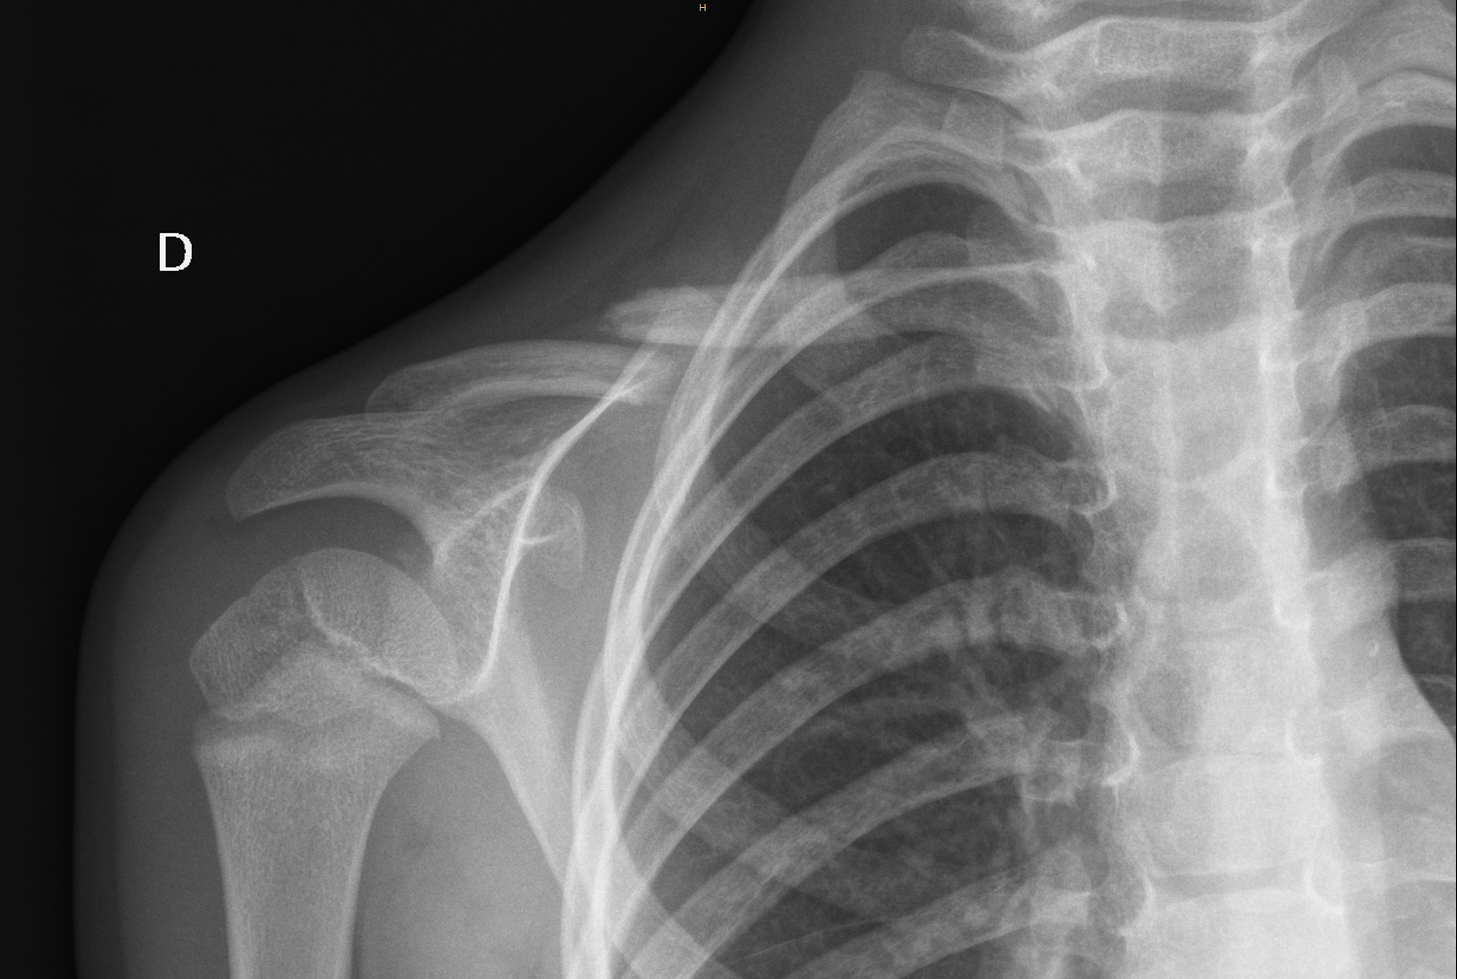

Fractura de clavicula real. Esta fractura puede afectar la zona proximal media o distal de la clavícula. Las fracturas de clavícula son un claro ejemplo de las múltiples fracturas de extremidad superior que pueden sufrir los deportistas. La clavícula conecta la parte superior del esternón con el omóplato. Algunas causas frecuentes de la fractura de clavícula son las caídas las lesiones deportivas y los traumatismos por accidentes de tránsito.

La clavícula puede fracturarse en tres zonas diferentes. Así los especialistas recomiendan medicamentos para aliviar el dolor como antibióticos o una inyección antitetánica si hay cortes en la piel y colocar una férula o cabestrillo para que la clavícula no sufra más daños y restringir. El lateral derecho sufre una fractura en su clavícula izquierda y el cuadro blanco ha informado que queda. Algunos deportes como aquellos que implican el uso de manillar motociclismo motocross ciclismo se desarrollan a altas velocidades lo que provoca en caso de traumatismo fracturas con relativa frecuencia.

Obtenga información sobre los síntomas de fractura de clavícula clavícula en recién nacidos niños adolescentes adultos y ancianos como dolor y hematomas en el sitio de la fractura. Ocurre cuando el deportista cae y se golpea directamente el hombro en la zona anterior. La fractura de clavícula es una lesión frecuente en particular en niños y adultos jóvenes.